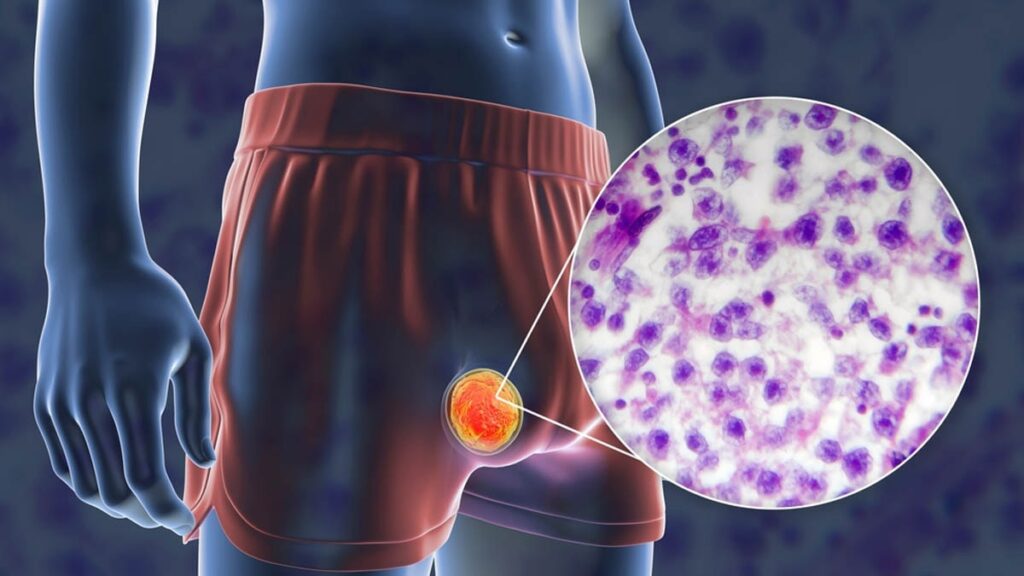

Testis Kanseri Belirtileri

Testis kanseri belirtileri şunları içerir:

- Testiste yumru veya şişlik

- Boyut değişiklikleri

- Skrotumda ağırlık hissi

- Testislerde ağrı

Skrotum Transillüminasyonu Testi

Kanserli yumruları tespit etmek için skrotumdan ışık tutularak transillüminasyon testi yapılır. Erken hareket her zaman tedavi gecikmesinden daha iyidir.